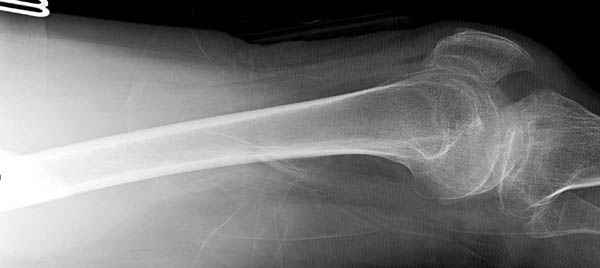

При поступлении бедро напряженное, сосудистых и неврологических расстройств нет. На рентгенограмме оскольчатый перелом бедра с вовлечением проксимальной спирали в шейку бедра.

Имя     : 2 injury lat.jpg

Тип     : image/jpeg

Размер  : 16253 байтов

Url     : http://weborto.net:8080/pipermail/ortho/attachments/20090531/91bb3dda/attachment-0004.jpg